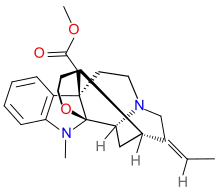

Indoles

- 18-Methoxycoronaridine

- 7-Acetoxymitragynine

- 7-Hydroxymitragynine

- ψ-Akuammigine

- Akuammidine

- Akuammine

- Coronaridine

- Eseroline

- Hodgkinsine

- Ibogaine

- Mitragynine

- Mitragynine pseudoindoxyl

- Noribogaine

- Pericine

- Pseudoakuammigine

Structures

| Indoles | ||||